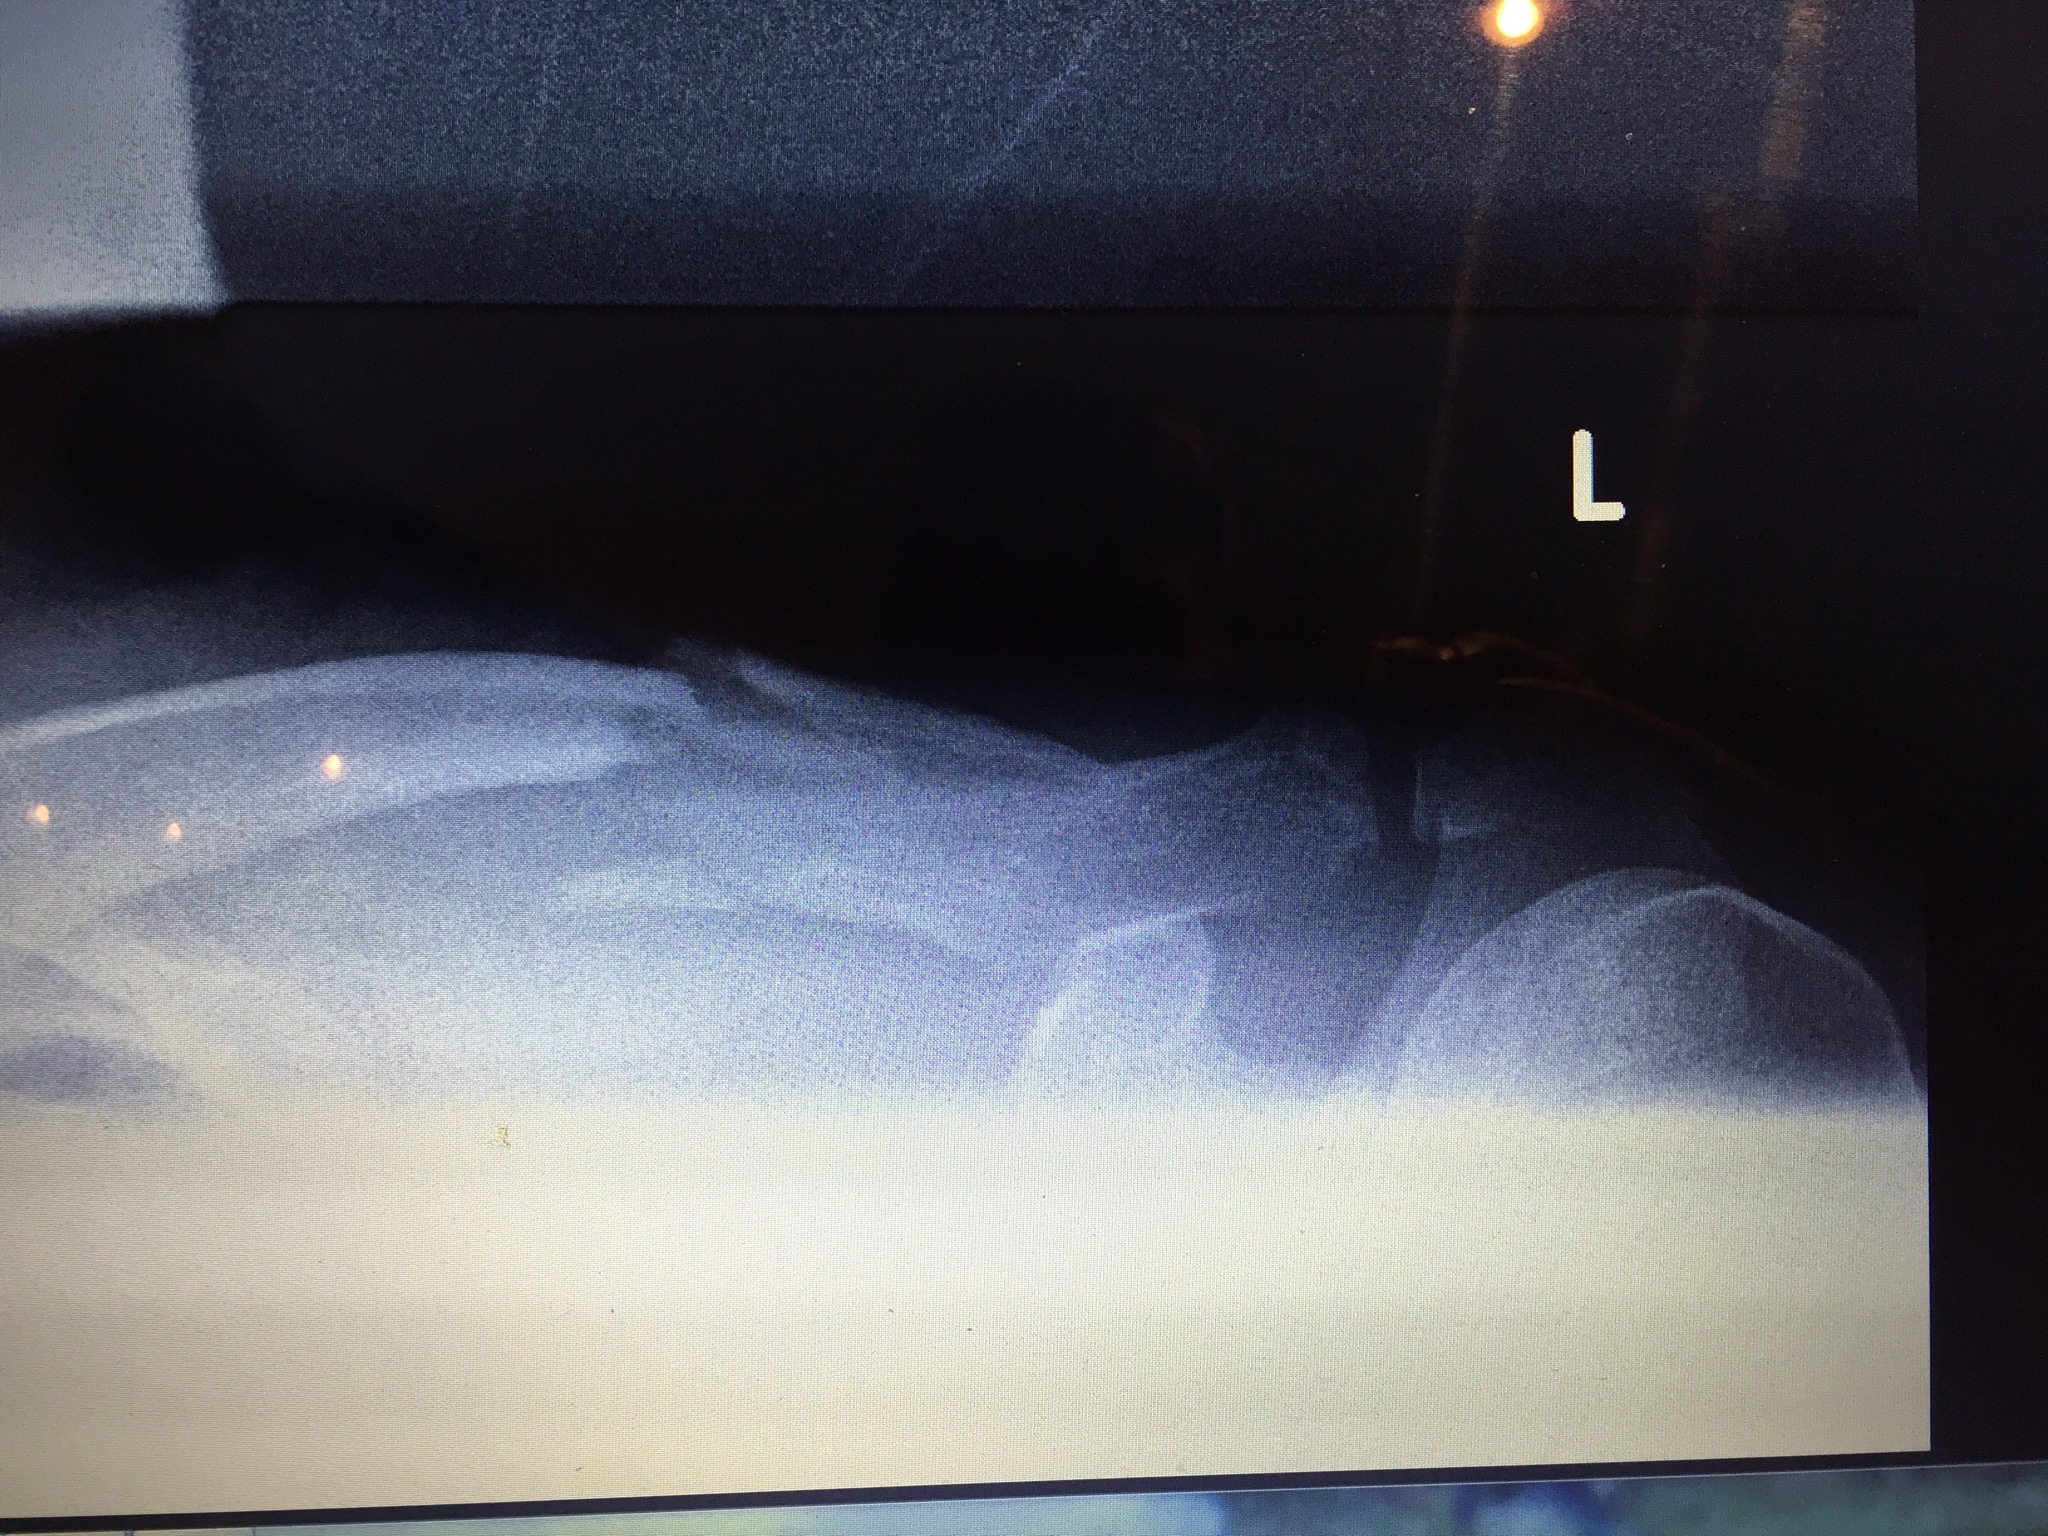

Und hier noch meine Baustelle, welche am Dienstag noch repariert wird :-( - linkes Schlüsselbein